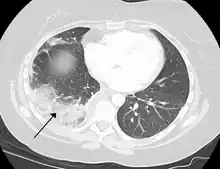

Chest CT (axial lung window)

Chest CT (coronal lung window)- Chest CT (axial lung window)